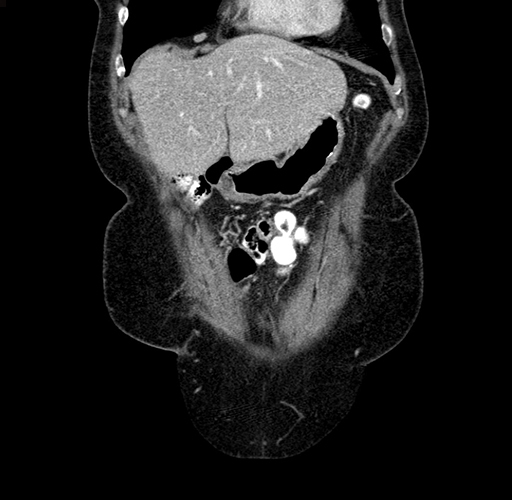

Pre-Chemo: Axial Venous

Pre-Chemo: Coronal Venous